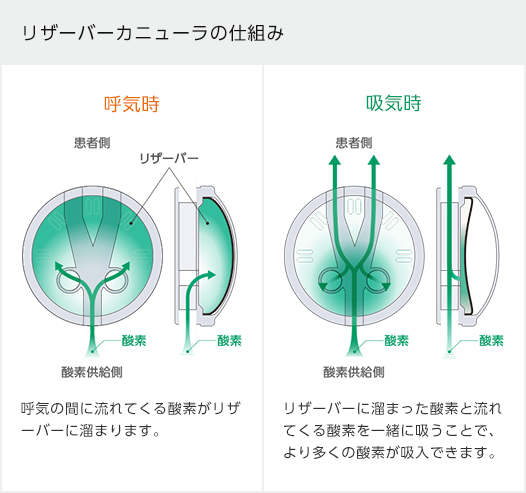

アトム リザーバーカニューラアトムメディカル株式会社。

アトム リザーバーカニューラアトムメディカル株式会社。

リザーバ式酸素供給カニューレオキシマイザー医療機器部日本ルフト株式会社。